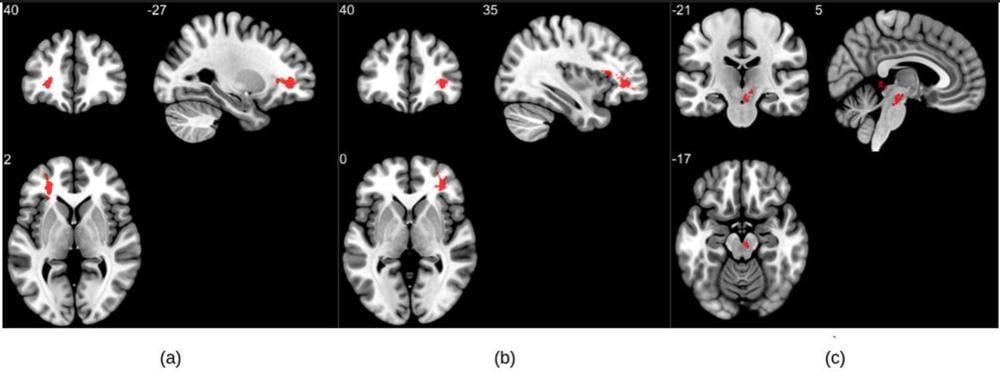

The researchers analyzed the susceptibility-weighted imaging data of 46 COVID-recovered patients and 30 healthy controls. Imaging was done within six months of recovery. Among patients with long COVID, the most commonly reported symptoms were fatigue, trouble sleeping, lack of attention and memory issues.

MRI results showed that patients who recovered from COVID-19 had significantly higher susceptibility values in the frontal lobe and brain stem compared to healthy controls. The clusters obtained in the frontal lobe primarily show differences in the white matter.

Portions of the left orbital-inferior frontal gyrus (a key region for language comprehension and production) and right orbital-inferior frontal gyrus (associated with various cognitive functions including attention, motor inhibition and imagery, as well as social cognitive processes) and the adjacent white matter areas made up the frontal lobe clusters.

The researchers also found a significant difference in the right ventral diencephalon region of the brain stem. This region is associated with many crucial bodily functions, including coordinating with the endocrine system to release hormones, relaying sensory and motor signals to the cerebral cortex and regulating circadian rhythms (the sleep-wake cycle).